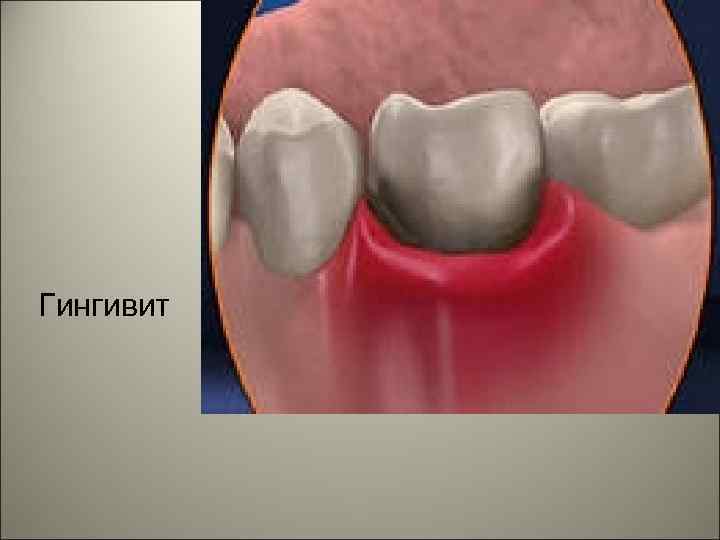

• Гингивит – группа заболеваний с развитием воспаления десны. Зубодесневое прикрепление при гингивите не нарушено.

• Клинически выявляемые воспалительные изменения десны появляются в детстве и с возрастом их частота растет. Пубертатный период характеризуется повышенной склонностью к развитию гингивита, при этом максимум приходится на возраст 11 лет (пубертатный гингивит).

• Затем заболеваемость снижается, а к 60 годам достигает практически 100%. Женщины болеют реже, чем мужчины. Развитие гингивита у женщин отмечается под влиянием повышенной концентрации прогестерона в период беременности (гингивит беременных) или применении некоторых гормональных контрацептивов.

• Считают, что прогестерон повышает проницаемость кровеносных сосудов десны, она становится более чувствительной к воздействию бактериальных, физических, химических факторов, способствующих развитию гингивита (прогестеронзависимый гингивит).

Гингивит